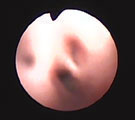

胸部気管の扁平化と気管分岐部周囲のtram line 胸部気管の気管支鏡所見。気管虚脱GradeII 気管虚脱は気管分岐部までみられた。 左後葉気管支では刀鞘型の気管支軟化がみられた。

経過:胸部レントゲンでは胸部気管の扁平化がみられた。動脈血酸素分圧は86.5mm Hgと正常範囲、動脈血炭酸ガス分圧は27.9mm Hgで換気障害はみられなかった。気管支鏡検査では、胸部気管において気管分岐部直前まで気管虚脱(GradeII)がみられ、左右後葉気管支に呼期に気管支が刀鞘型に潰れる気管支軟化症もみられた。粘膜は全体的に浮腫状を呈していた。気管支肺胞洗浄液(RB2, 回収率24%)では細菌・真菌は検出されず、軽度好中球の増加(15.75%)がみられマクロファージが活性化していた。細胞の背景には非常に細かい塵埃状物が多数みられた。気管・気管支軟化症をともなった慢性気管支炎と診断された。飼い主の家庭には1日20本程度の喫煙者が2人居り、犬の受動喫煙も原因のひとつである可能性が示唆された。現在、気管支拡張剤とステロイド剤の間欠投与で咳はコントロールしている。